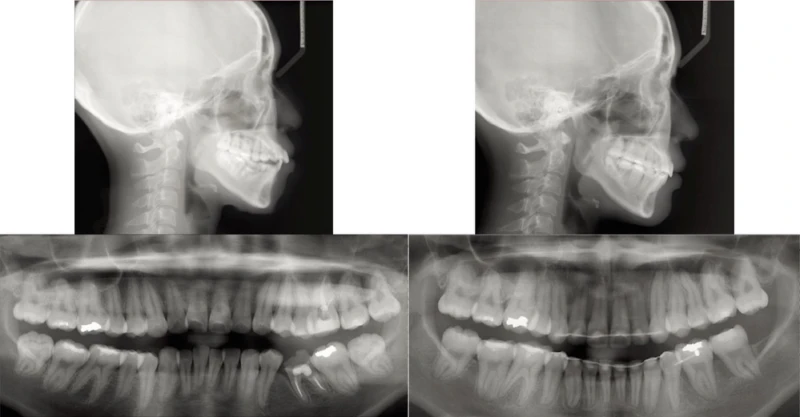

– Xương: Tương quan xương loại I (SNA 85°, SNB 80°, ANB 5°), góc mặt phẳng hàm dưới lớn (SN-MP 41°)

– Mặt: Vẩu hai hàm, môi căng

– Răng: Tương quan răng hàm loại I bên phải và loại III bên trái. Đường giữa răng dưới lệch sang trái 2mm so với đường giữa mặt, góc răng cửa dưới so với mặt phẳng hàm dưới 91°, chen chúc răng dưới nặng (thiếu khoảng hơn 7mm), độ cắn chìa răng cửa là 7mm. Mất răng 35, răng 36 điều trị tuỷ không tốt. Các giá trị trên phim đo sọ được tổng hợp ở Bảng. Chỉ số lệch lạc DI của ABO là 25.

Hình 7 Phim toàn cảnh và phim đo sọ trước điều trị cho thấy môi căng, mất răng 35 và răng 36 điều trị tuỷ không tốt

Hình 8 Phim toàn cảnh và phim đo sọ sau điều trị cho thấy môi cân bằng, độ nghiêng gần-xa chân răng 34 và 47 chưa hợp lý